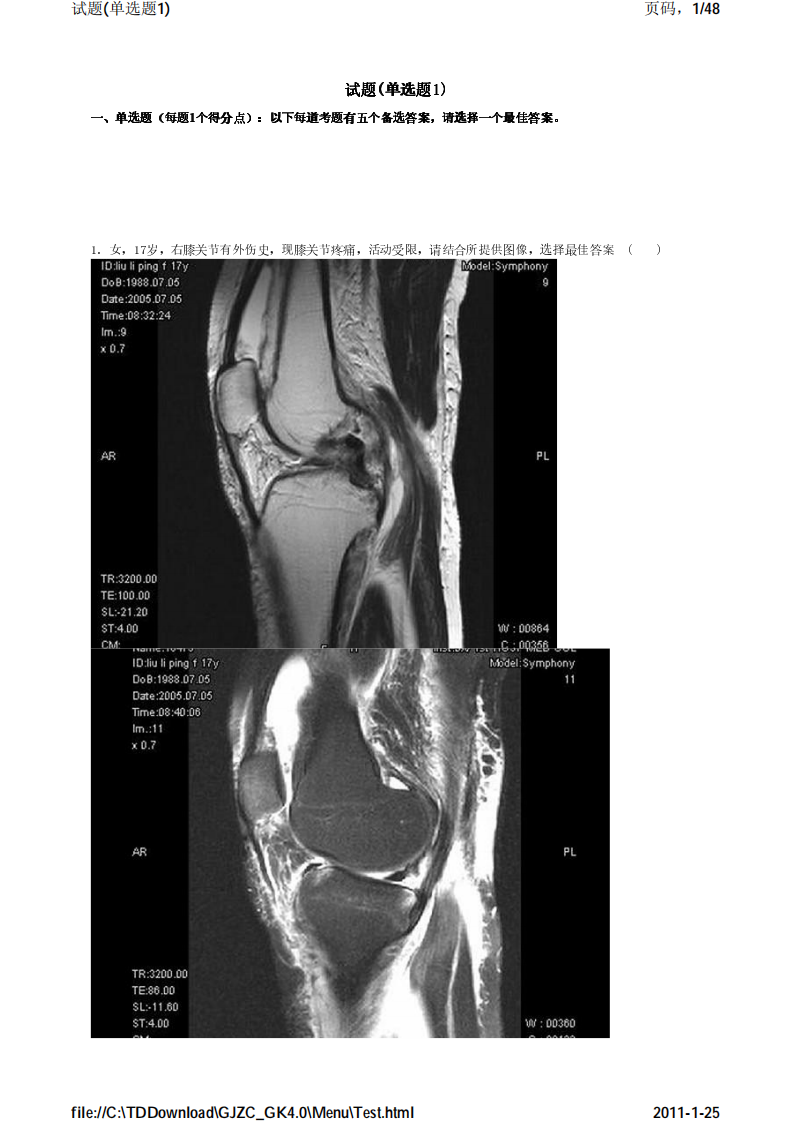

考试宝典 医学高级职称考试 骨科 单选题1.pdf

骨科